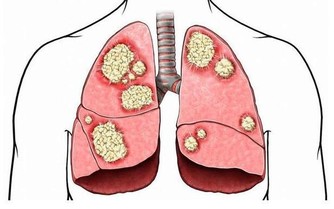

體重與壽命呈“U”形關係,肥胖者與消瘦者壽命都會縮短。人體需要一定的脂肪來儲藏體能,幫助抵禦疾病。瘦弱的中老年人,其身體的新陳代謝和各種生理功能都比常人低,體質較弱,容易患感冒、發熱、慢性支氣管炎、肺炎、肺結核等呼吸道疾病及消化不良、胃炎、胃潰瘍、腸炎等消化道疾病。